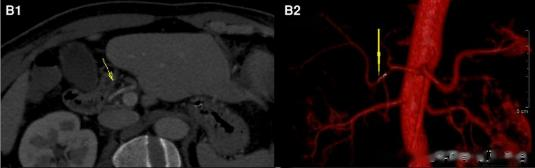

放射科对患者的 CT 图像进行了处理及三维重建后 , 发现鱼刺正位于肝动脉内 。 黄斌教授立即联系超声科进一步定位 , 看鱼刺是否损伤或穿破了肝动脉或造成肝脏血运障碍 。 超声检查和胸腹主动脉 CT 血管造影均提示:肝动脉内有鱼骨样异物 , 暂时未对血管壁造成损伤 , 并对鱼刺的确切位置进行了成像定位 。

图 B1、B2:胸腹 CT 血管造影检查结果:鱼刺位于箭头所指位置